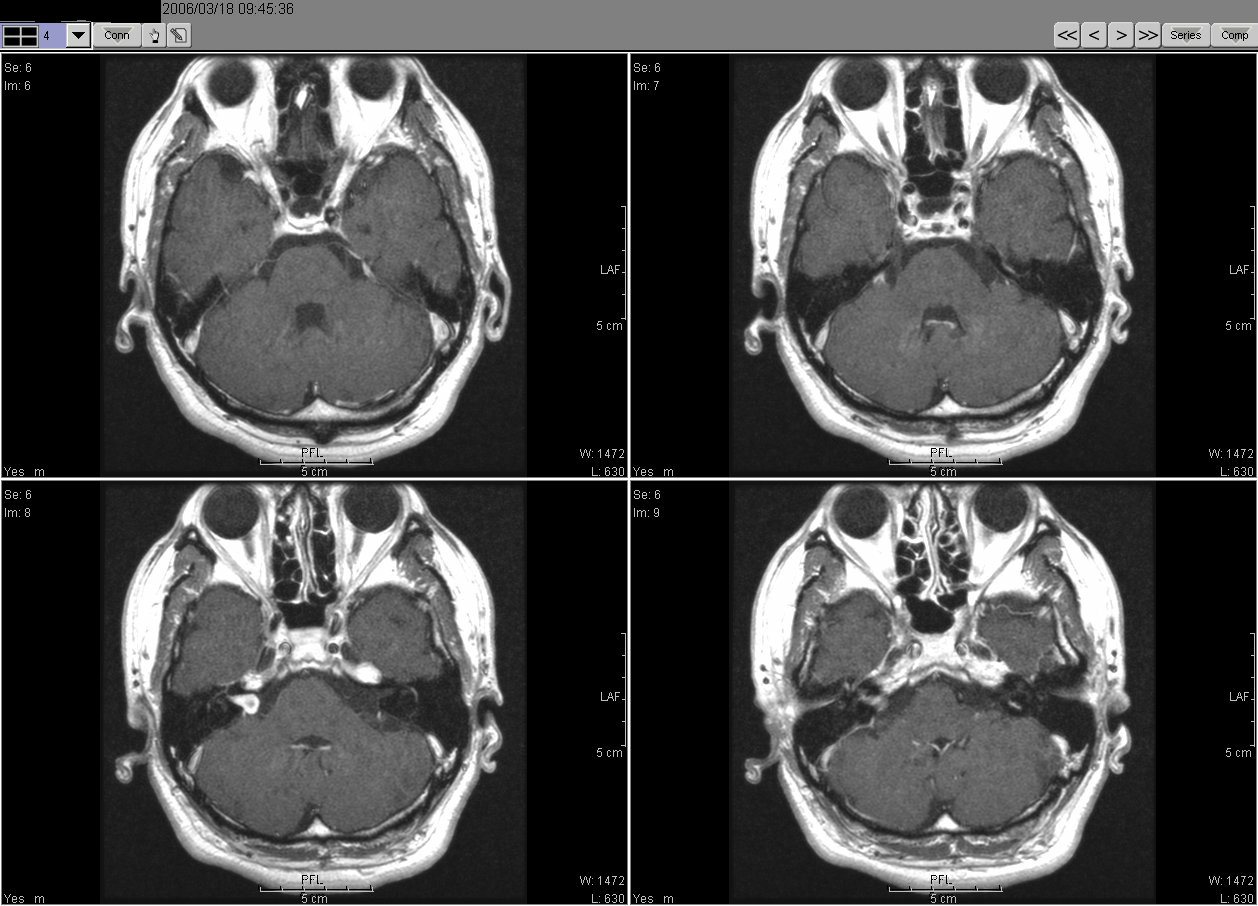

2006_03_18 MRI

2006_03_18MRI02